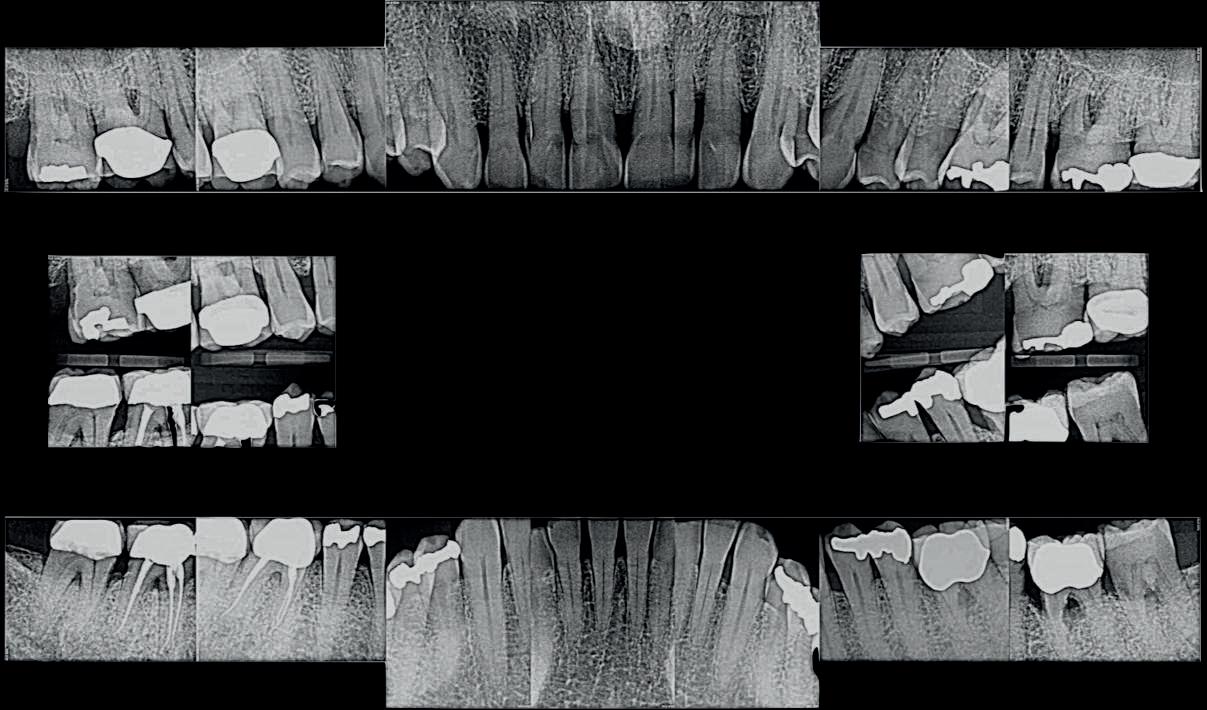

Examinarea parodontală a relevat sângerări generalizate la sondare și adâncimi de sondare de până la 9 mm la molarii maxilari și mandibulari, cu multiple furcații implicate la fiecare molar (fig. 2-7). Prezenta mobilitate multiplă de clasa I la dinții posteriori și de clasa II la dinții nr. 16 și 21 (molarul prim maxilar drept și incisivul central maxilar stâng).

Parodontologul a decis să evalueze dintele nr. 16 în privința PRS, deoarece acesta era molarul cel mai afectat parodontal care urma să fie tratat și menținut pe arcadă (fig. 2 și fig. 8). Acest dinte (molarul prim maxilar drept = scor 1) prezenta adâncimi de sondare de 7 mm (scor 1); trei invazii totale de furcație (scor 3) (mezial [furcație de grad II], vestibular [furcație de grad I] și distal [furcație de grad II]); și mobilitate de clasa II (scor 2). Valoarea totală a PRS pentru dintele 16 a fost de 8, reprezentând un prognostic „rezervat”. Pe baza acestui scor, probabilitatea de a nu pierde niciun dinte din cauza bolii parodontale timp de 15 ani a fost de 81%, iar pentru 30 de ani probabilitatea a fost de doar 56% (fig. 9).

pacientul a fost reevaluat la 3 luni și a început faza de menținere parodontală a tratamentului (adică, SPT) sub îngrijirea parodontologului, la fiecare trei luni, din cauza stării avansate a bolii parodontale, cu invazii multiple în furcațiile molarilor, alături de examinările restaurative anuale și radiografii bitewing la cabinetul medicului stomatolog generalist.

Parodontologul a considerat că dinții nr. 38 și 37 (molarul trei și doi stâng inferior) aveau un prognostic discutabil din cauza pierderii severe a atașamentului parodontal, a furcațiilor de clasa III și a probabilelor carii de furcație detectate pe radiografii. Acești doi dinți au fost tratați la fel ca ceilalți, pacientul fiind avizat că ar putea necesita fie un retratament parodontal, fie extracție, cu posibile recomandări de implanturi în viitor.

Pe parcursul ședințelor de întreținere parodontală ulterioare, valoarea PRS pentru dintele nr. 16 a fost redus la un scor de 5, un prognostic „bun”, cu o probabilitate de 93% de a-și păstra dinții din punct de vedere parodontal după 15 ani și o probabilitate de 80% de a obține acest lucru după 30 de ani. Scorul de implicare a furcației s-a redus, iar furcația vestibulară a dintelui nr. 16 a devenit improbabilă (scor = 1). Scorul de mobilitate a dintelui nr. 16 a fost redus cu 1 (scor = 1).

Pacientul a rămas în întreținere parodontală la fiecare 3 luni până în 2018, având o complianță excelentă. Reevaluarea scorului său PRS la fiecare ședință a consolidat rezultatele pozitive ale tratamentului și importanța complianței sale față de „cheile pentru succes”. Valoarea lui PRS pentru dintele nr. 16 a rămas stabil (scor 5).

inferiori stângi nr. 37 și 38, pe care a decis să îi retrateze prin terapie parodontală asistată de laser. Acest retratament a reușit să elimine simptomele și a condus la stabilitate parodontală (fig. 10-13).

7. Rx periapicale înainte de tratament.

8. Rx periapicală a molarului prim maxilar drept (identificat ca fiind molarul cel mai afectat parodontal care era planificat să fie menținut pe arcadă).

13. Rx periapicale la 4 ani după tratament. Se observă absența pierderii osoase progresive în comparație cu fig. 7, adică, fără semne de boală parodontală activă.